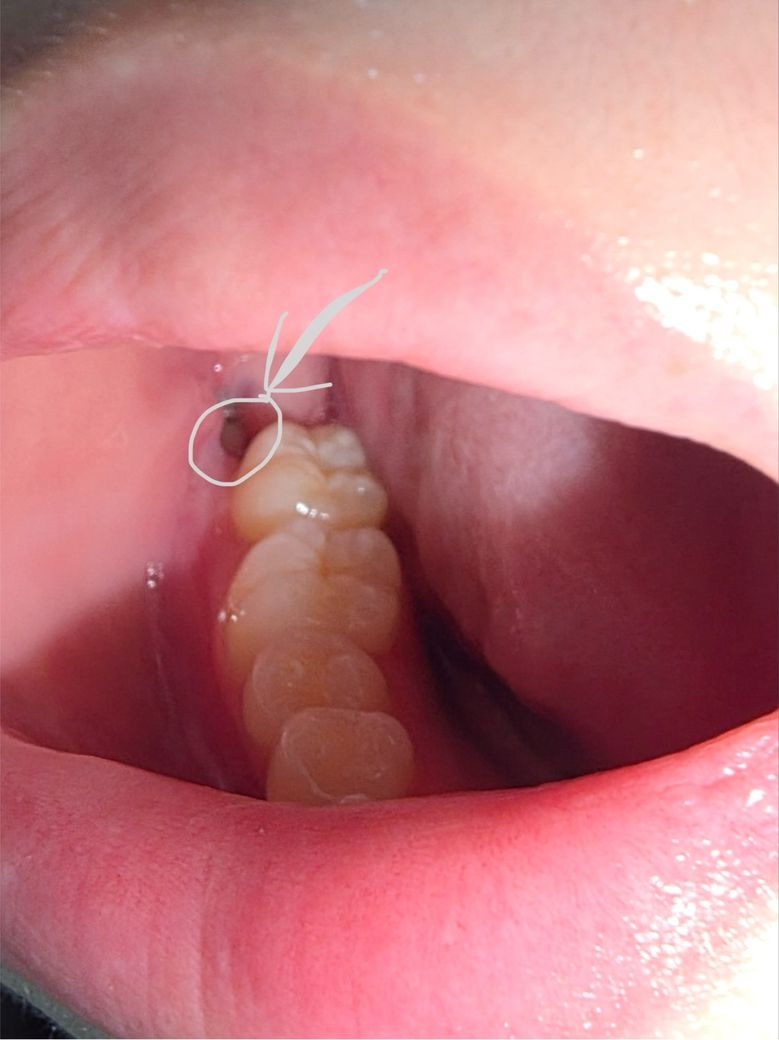

사랑니 발치 후 이물질인가요 피브린이 떨어진건가요

아래 매복 사랑니 발치 후 일주일 뒤 실밥 제거했고,

실밥제거한지 3일째입니다

국밥을 먹은 후 확인하니 흰색 무언가가 있는게 보이는데, 밥인지 원래 있던건지 모르겠어서

가글, 양치로 제거가 안되길래

물을 넣어 여러번 쏴봤는데 안 떨어져서 그냥 냅뒀다가

그 다음 식사 후 이물질 제거할 겸 물을 쐈는데 갑자기 제거가 되었습니다.

피가 나거나 하진 않는데

피브린이라면 이렇게 제거가 되기도 하나요?

이물질일 가능성이 높나요?

그리고 매일 하루에 한 번 정도 주사기로 구멍 세척해도 되나요?

• 1번 째 사진

사진상에 보이는건 발치후에 잇몸이 치유되면서 생기는 자연스러운 현상이니 억지로 제거를 하실필요가 없습니다.

사진사으로는 특별히 문제가 없이 잘 낫고 있어보입니다. 주사기로 구멍 세척하셔도 됩니다.

발치를 한부위를 주사기로 청소하거나 하면 안됩니다. 출혈이 되고 혈병이 제거되기 때문입니다. 음식물이 끼면 가볍게 가글을 해주는것이 좋습니다.

1. 이물질이 나온 것 같습니다. 걱정마세요

2. 주사기로 세척 권장합니다 물 살짝 쏴주세요

3. 사진상으로 별 문제 없어보입니다